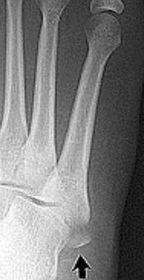

What type of fracture is this? | Avulsion fracture |